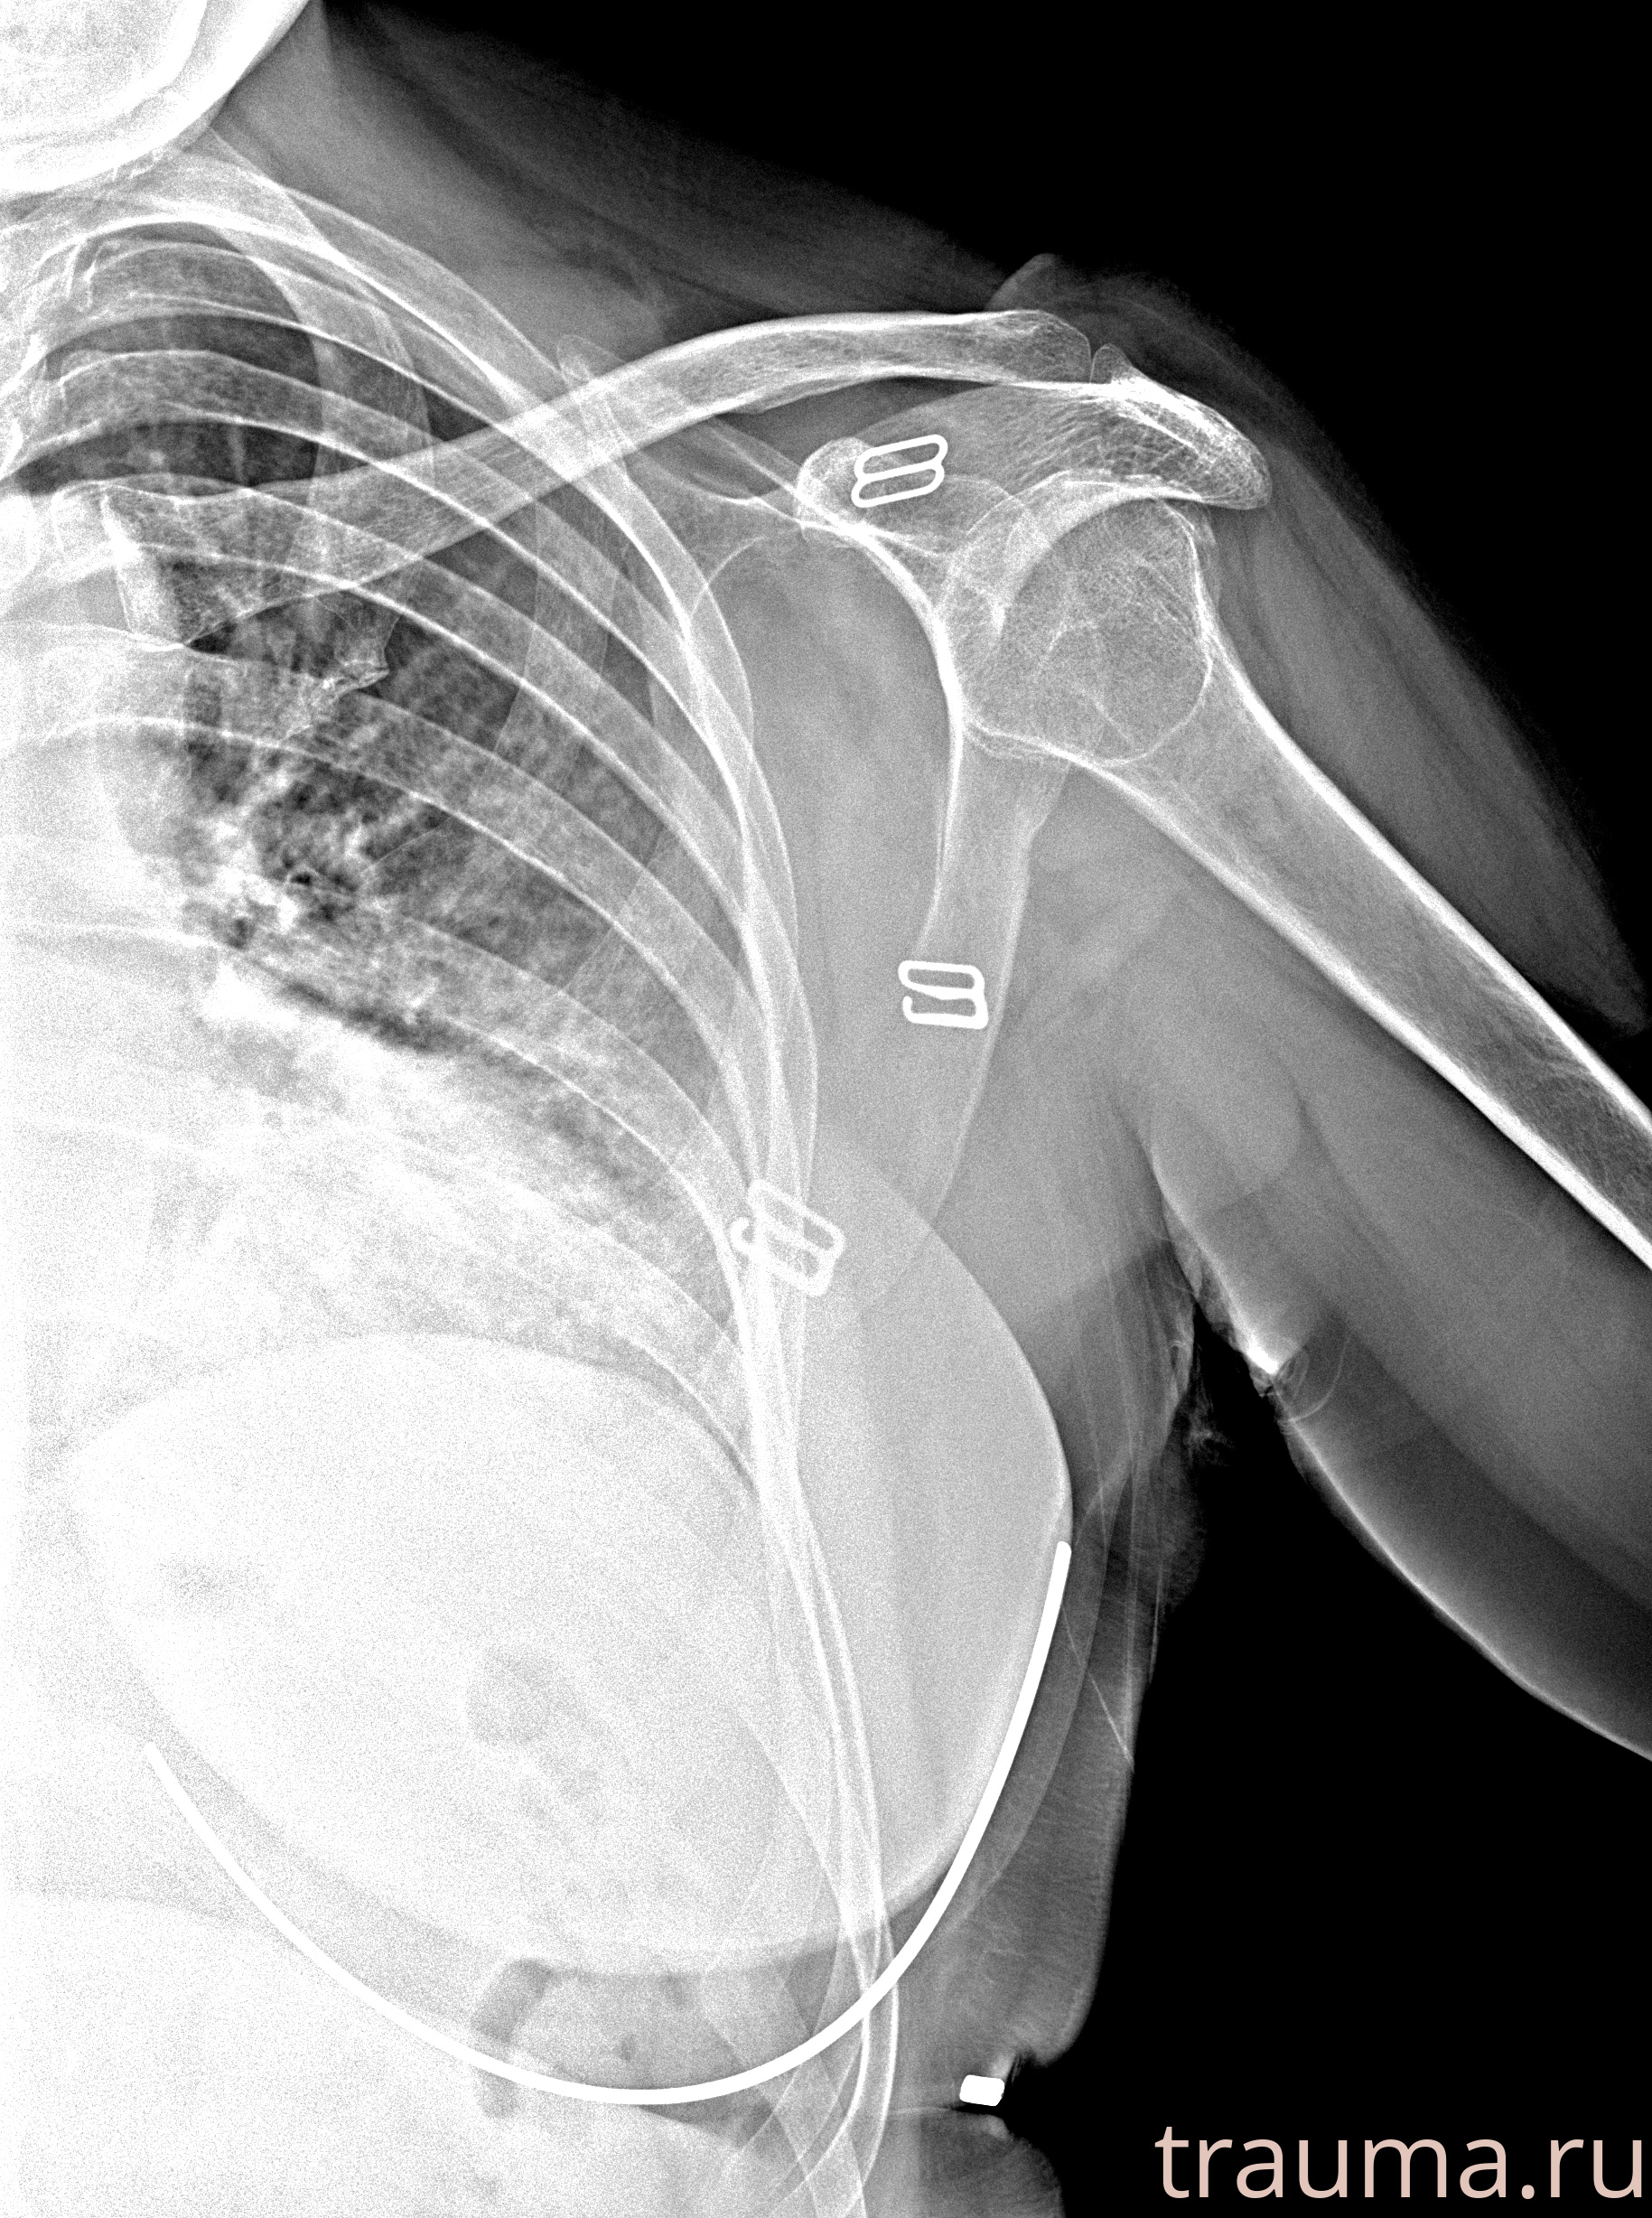

Рентгенограммы

Рентген на дому: по вашему адресу приезжает врач-рентгенолог, травматолог-ортопед с мобильным рентгеновским аппаратом, проводит диагностику травмы или заболевания, делает необходимые рентгенограммы, дает рекомендации по дальнейшему лечению. Получить качественные снимки в домашних условиях возможно благодаря уникальной методике, разработанной МосРентген Центром для института  Склифосовского